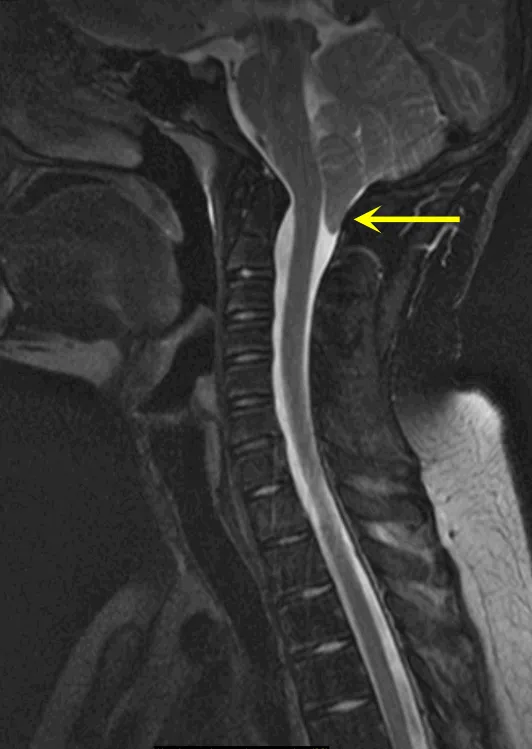

"原以为是颈椎劳损"。病情在24小时内急剧恶化:从颈部酸痛发展为剧烈呕吐,最终在救护车上失去颈部以下所有知觉。急诊初步诊断为脊髓血管病变,住院11天期间左侧躯体部分恢复知觉,但右侧...

更新时间:2026-01-16 10:31:16